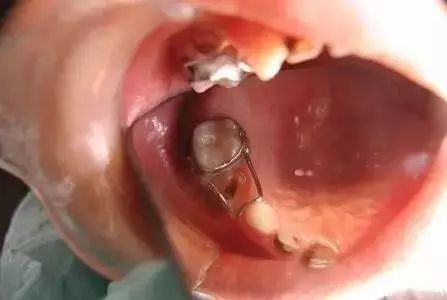

lmq-j033阻萌器产品名称:活动矫治器注册证号:渝械注准20182170174

远中导板式间隙保持器:适用于第二乳磨牙早失,第一恒磨牙尚未萌出或萌